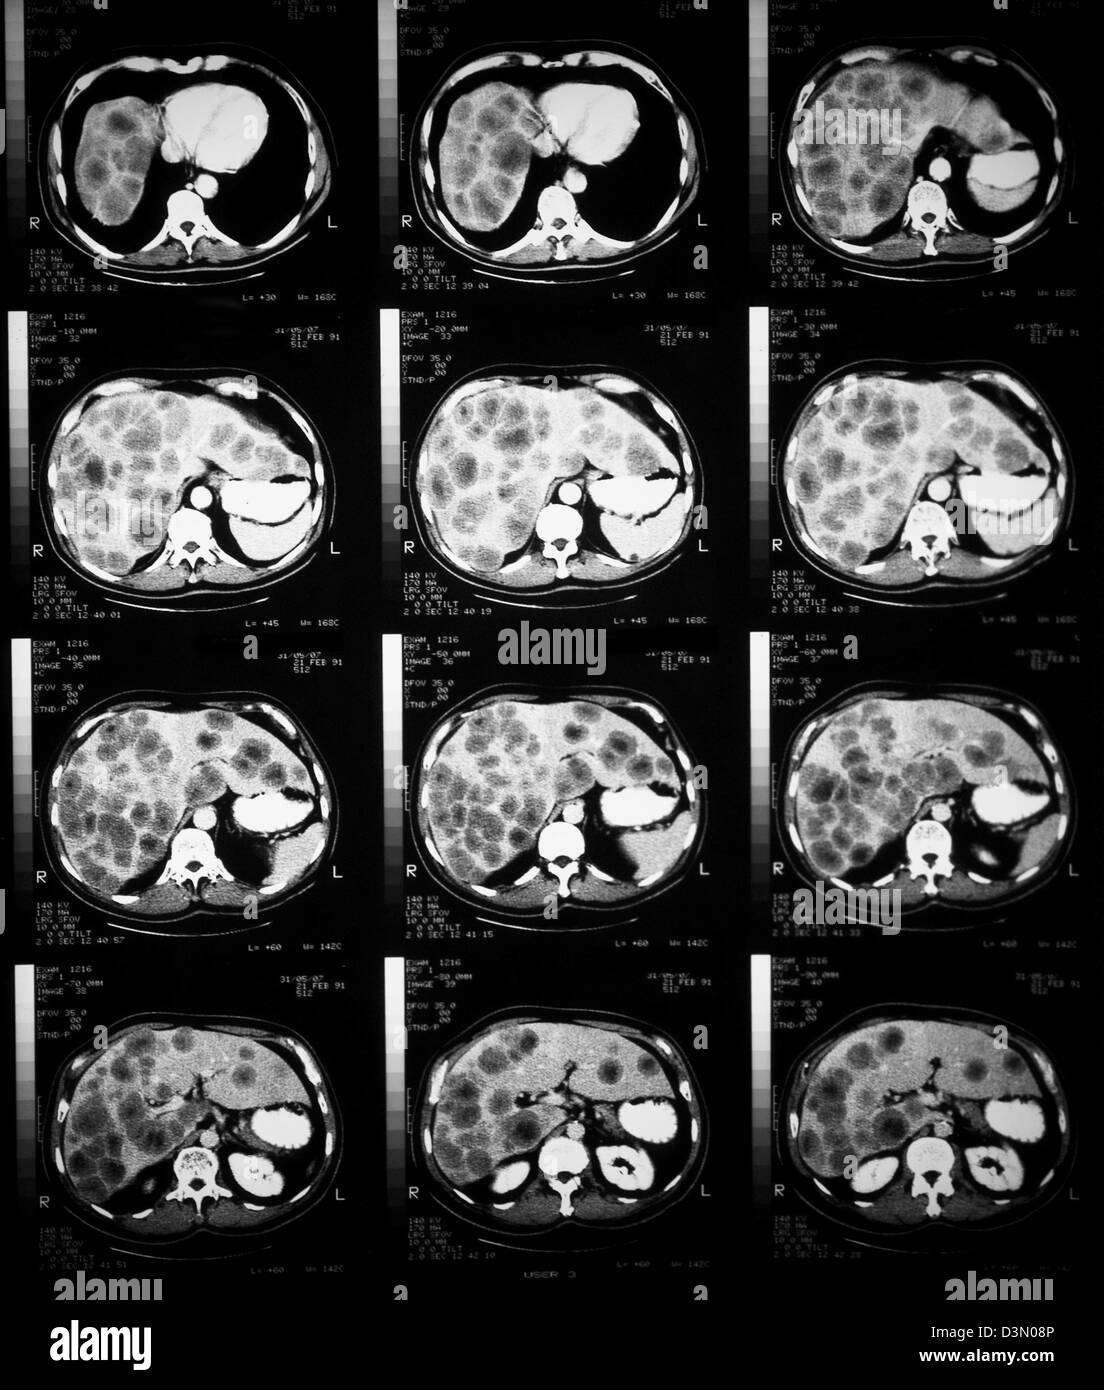

CT scan slices showing extensive metastatic liver cancer Stock Photo What Does Liver Cancer Look Like On An Mri most people don’t notice any signs of liver cancer early on. When they do show up, you may: hepatocellular carcinoma (hcc) is the most common primary liver cancer. have increased knowledge regarding the. magnetic resonance imaging (mri) is the modality of choice for liver imaging due to its superior contrast. Staging tests help determine the size.. What Does Liver Cancer Look Like On An Mri.

From www.alamy.com

CT scan slices showing extensive metastatic liver cancer Stock Photo What Does Liver Cancer Look Like On An Mri Feel full easily or not. When they do show up, you may: most people don’t notice any signs of liver cancer early on. liver imaging in patients with a history of known or suspected malignancy is important because the liver is a common. Sometimes they can tell a benign tumor from a malignant one. Staging tests help determine. What Does Liver Cancer Look Like On An Mri.